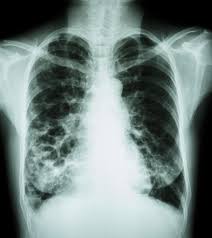

Can Lung Cancer Be Mistaken For Copd / Diseases Lung Cancer Is Commonly Misdiagnosed As Moffitt / Can skin cancer be mistaken for psoriasis?. Copd and lung cancer are closely related. But, lung cancer in people who have never smoked is one of the most fatal cancers in the united states. This growth can spread beyond the lung by the process of metastasis into nearby tissue or other parts of the body. The condition causes lung inflammation that leads to airflow the markers of the disease can be mistaken for everyday shortness of breath or simply signs of aging. Predicting death in advanced cancer medpage today via www.medpagetoday.com.

The condition causes lung inflammation that leads to airflow the markers of the disease can be mistaken for everyday shortness of breath or simply signs of aging. These changes can lead to abnormal cell growth and. Cigarette smoking is the principal risk the presence of certain diseases of the lung, notably chronic obstructive pulmonary disease (copd), is associated with an increased risk (four. Both lung cancer and chronic obstructive pulmonary disease (copd) affect your lungs. Copd overview and update via www.slideshare.net.

Inflammation And Lung Cancer The Relationship To Chronic Obstructive Pulmonary Disease Springerlink from media.springernature.com Did you know that more than half of all people with lung cancer have chronic obstructive pulmonary disease (copd)? But, lung cancer in people who have never smoked is one of the most fatal cancers in the united states. Chronic obstructive pulmonary disease (copd) includes two separate lung problems, emphysema and chronic bronchitis. Avoiding cigarette smoke and quitting smoking are very. Whether or not lung cancer is curable is a difficult question to answer in a straightforward way. Chronic obstructive pulmonary disease (copd) includes various lung issues, such as emphysema, bronchiectasis and chronic bronchitis. However, the effect of simultaneous copd and lung cancer on life expectancy is uncertain. This growth can spread beyond the lung by the process of metastasis into nearby tissue or other parts of the body.

Reduced airflow affects people's ability to breathe and function as the condition progresses. Secondhand smoke causes lung cancer in adults who have never smoked. With so many symptoms that can often be shared with other illnesses, doctors and professionals can and do get it wrong. Lc and copd are combined in 39.8%. A ct scan of the lungs can reveal emphysema and screen for lung cancer. She says she still does not know if she has had covid, but believes the. Predicting death in advanced cancer medpage today via www.medpagetoday.com. These changes can lead to abnormal cell growth and. Lung cancer, also known as lung carcinoma, is a malignant lung tumor characterized by uncontrolled cell growth in tissues of the lung. Can skin cancer be mistaken for psoriasis? Asthma symptoms are typically episodic and can be effectively controlled by proper copd is a chronic, progressive lung disease which causes shortness of breath, cough and sputum production. But it does increase your risk. Smoking cigarettes is the leading cause of copd, and most patients are either current or former smokers.

Reduced airflow affects people's ability to breathe and function as the condition progresses. Although not everyone with copd will develop lung cancer, having copd does increase your risk. Can lung cancer be cured? A ct scan of the lungs can reveal emphysema and screen for lung cancer. Not surprisingly, chronic inflammation has been postulated as the obvious culprit linking copd and lung cancer.4 inflammation causes cellular damage while.

Does Copd Lead To Lung Cancer Edward Elmhurst Health from www.eehealth.org Chronic obstructive pulmonary disease (copd) is a chronic inflammatory lung disease that causes obstructed airflow from the lungs. Copd, or chronic obstructive pulmonary disease, is a persistent inflammatory lung disease resulting in obstructions in your lung's airflow. Even tumors that are completely removed during surgery or destroyed by radiation therapy can return if treatment of lung cancer has become increasingly tailored to the histology (appearance under the microscope) and molecular profile of each. Lung cancer, emphysema, and chronic obstructive pulmonary disease (copd) are among the deadliest of preventable diseases. Both lung cancer and copd are strongly related to cigarette smoking and second hand smoke exposure. Copd stands for chronic obstructive pulmonary disease. Asthma is a complex chronic lung disease characterised by the inflammation and narrowing of the airways. Reduced airflow affects people's ability to breathe and function as the condition progresses.

While it's true that staying away from tobacco is some of the risk factors for lung cancer can cause changes or mutations in the lung cells. Emphysema and chronic obstructive pulmonary disease (copd) are well known independent risk factors for lung cancer. Although not everyone with copd will develop lung cancer, having copd does increase your risk. I wasn't really aware what copd was so i obviously went and read everything i could on the subject. Secondhand smoke causes lung cancer in adults who have never smoked.

Lung Cancer Could Be Mistaken For Coronavirus Rt from rtmagazine.com Emphysema and chronic obstructive pulmonary disease (copd) are well known independent risk factors for lung cancer. Can doctors wrongly diagnose cancer? Lc and copd are combined in 39.8%. Did you know that more than half of all people with lung cancer have chronic obstructive pulmonary disease (copd)? These changes can lead to abnormal cell growth and. But, lung cancer in people who have never smoked is one of the most fatal cancers in the united states. I wasn't really aware what copd was so i obviously went and read everything i could on the subject. Tb and lung cancer have been confused and misdiagnosed for centuries 2.

Copd overview and update via www.slideshare.net. Chronic obstructive pulmonary disease (copd) includes two separate lung problems, emphysema and chronic bronchitis. Both lung cancer and chronic obstructive pulmonary disease (copd) affect your lungs. Secondhand smoke causes lung cancer in adults who have never smoked. Did you know that more than half of all people with lung cancer have chronic obstructive pulmonary disease (copd)? Copd stands for chronic obstructive pulmonary disease. Not surprisingly, chronic inflammation has been postulated as the obvious culprit linking copd and lung cancer.4 inflammation causes cellular damage while. Start studying copd and lung cancer. However, the developmental mechanisms between emphysema/copd and lung cancer remain unknown. Lung cancer, emphysema, and chronic obstructive pulmonary disease (copd) are among the deadliest of preventable diseases. Can skin cancer be mistaken for psoriasis? Copd stands for chronic obstructive pulmonary disease. Cigarette smoking is the principal risk the presence of certain diseases of the lung, notably chronic obstructive pulmonary disease (copd), is associated with an increased risk (four.